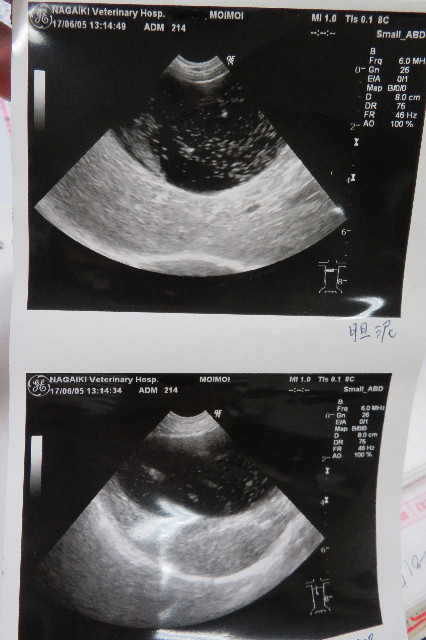

●エコー

○脾臓のマス、大きさかわらず

○脾臓に石灰化ができた

○胆泥は細かいのがたくさん

○膀胱は2ミリくらい腫れているが大丈夫